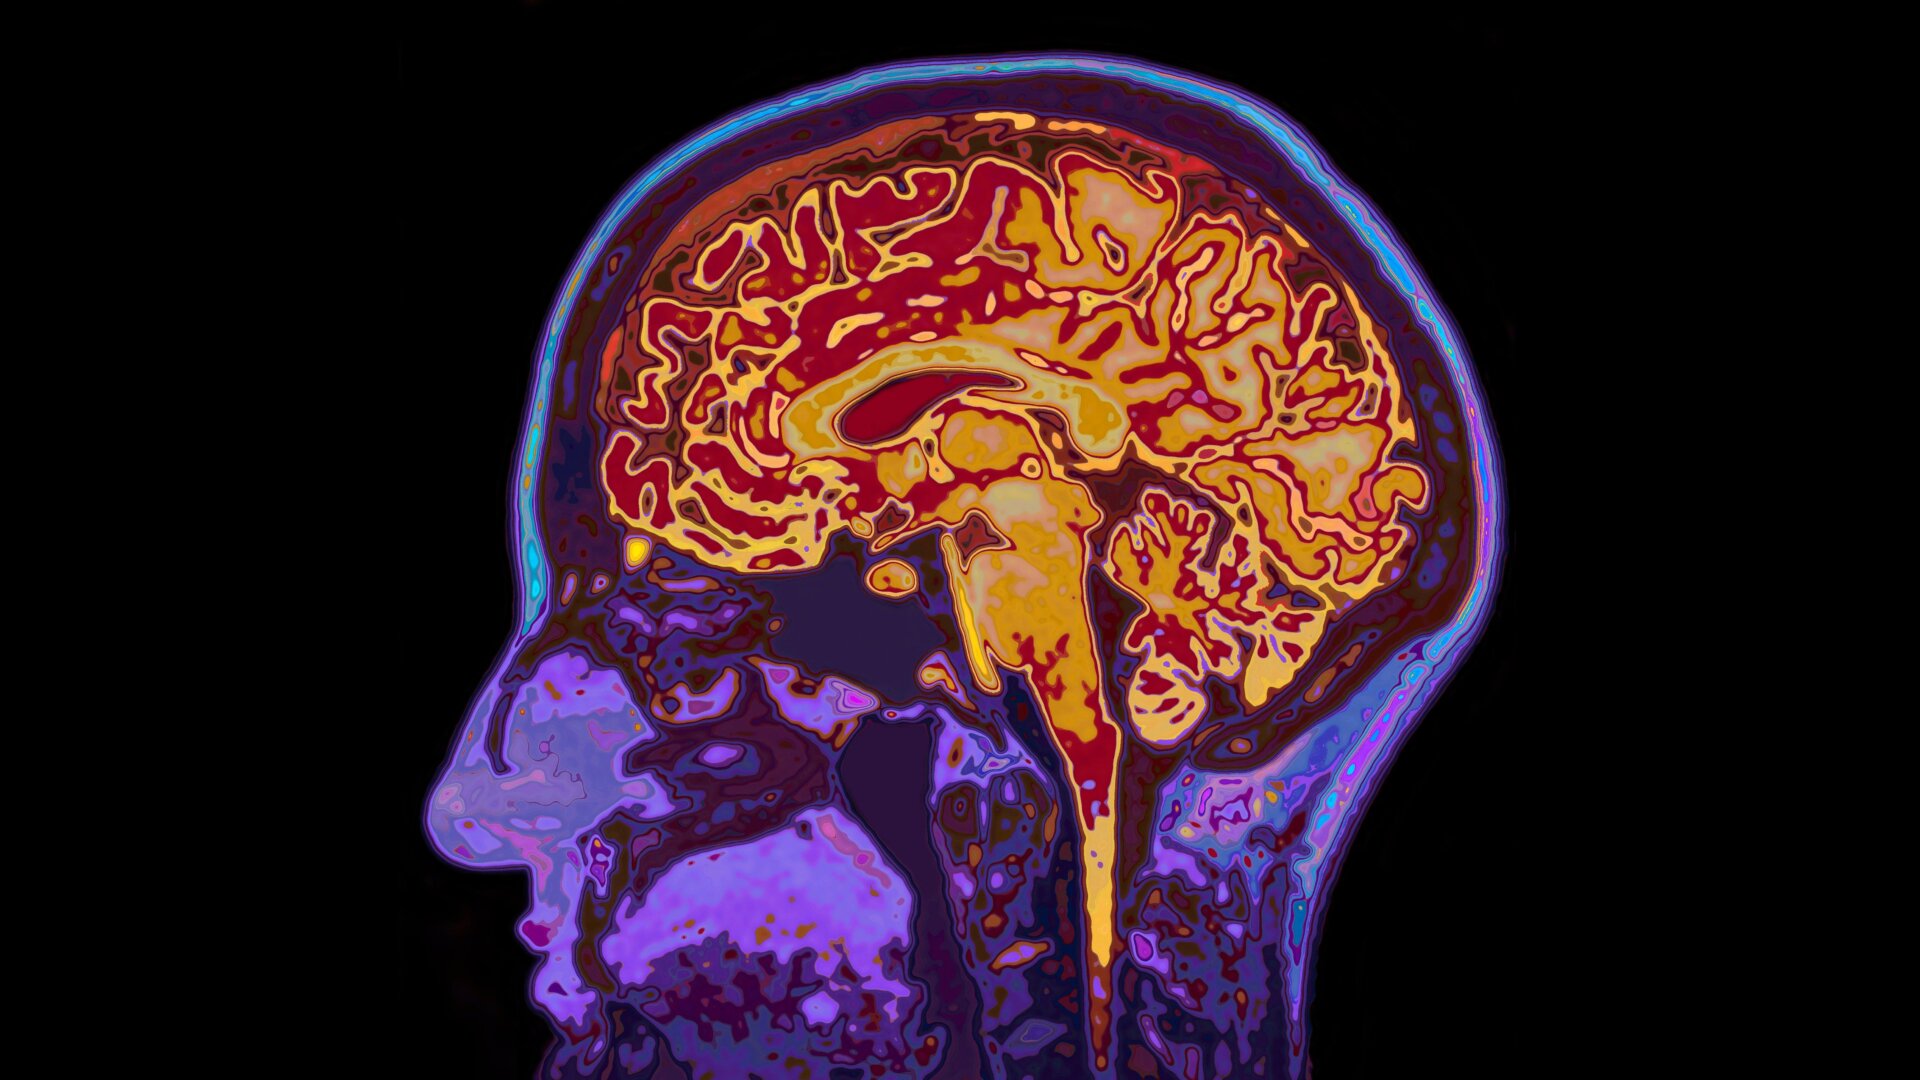

The treatment is known as lecanemab, and it’s being co-developed by the pharmaceutical companies Biogen and Eisai. It’s a lab-made antibody designed to target amyloid beta, a protein naturally found in the brain that’s thought to play a pivotal role in causing Alzheimer’s disease. In those with Alzheimer’s, hardened clumps of amyloid known as plaques build up over time, and these plaques seem to help destroy healthy brain tissue. It’s been theorized that giving lecanemab or similar drugs to patients in the early stages of Alzheimer’s can delay or stop the progression of their condition by reducing the brain’s supply of these amyloid plaques.